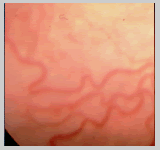

PROLIFERACIÓN NEOVASCULAR PLANA:

En la enfermedad clásica la proliferación neovascular

se produce sobre el ridge y se extiende luego hacia el vítreo,

sin embargo en la ROP en zona I la neovascularización se

produce en el plano de la retina. Clínicamente observaremos

la neovascularización como un color rosado o rojizo en la

retina periférica vascular cercano al limite con la retina

avascular (Foto A) o como pequeños focos de neovascularización

sobre la retina vascular (Foto B).